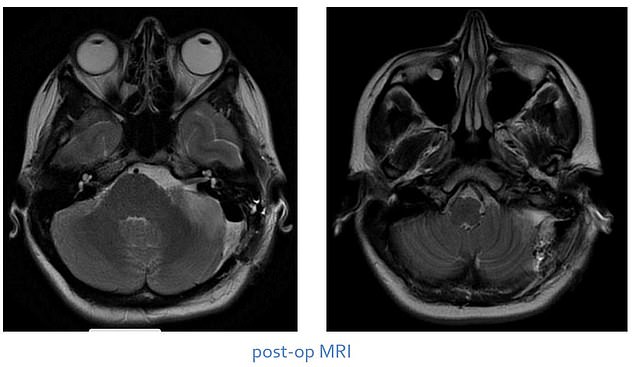

During a six-hour surgery, Dr Hadjipanayis resected 100 percent of Giuffrida's tumor.

'We were able to get it off of her hearing nerve, the nerves that control her face, and the nerves that allow her to swallow and speak,' he said.

Giuffrida's swallowing and hearing improved, but she needed about a week of rehabilitation for her balance. Pictured: Scans of Giuffrida's brain after the operation

Giuffrida spent about two weeks in recovery, where improvements were seen almost immediately.

Dr Hadjipanayis said Giuffrida's swallowing and hearing improved, but she needed about a week of rehabilitation for her balance.